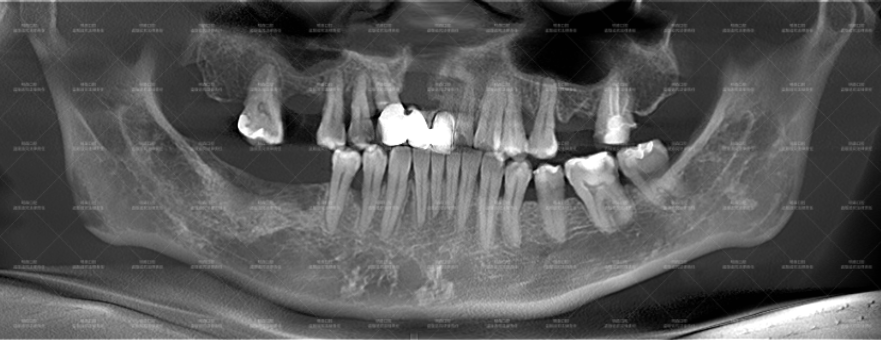

经过多月治疗炎症明显改善:

患者CT全景片中的阴影明显淡化,牙齿矫正后已排列好。